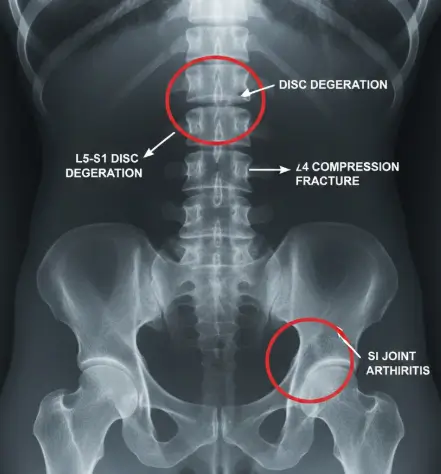

Accurate diagnosis of back pain involves evaluating the spinal column, including the lumbar spine, thoracic spine, intervertebral discs, facet joints, ligaments, muscles, and spinal nerves. Common diagnostic methods include:

• X-rays to detect bone abnormalities, fractures, or degenerative changes

• MRI scans to visualize herniated discs, nerve compression, and soft tissue injury